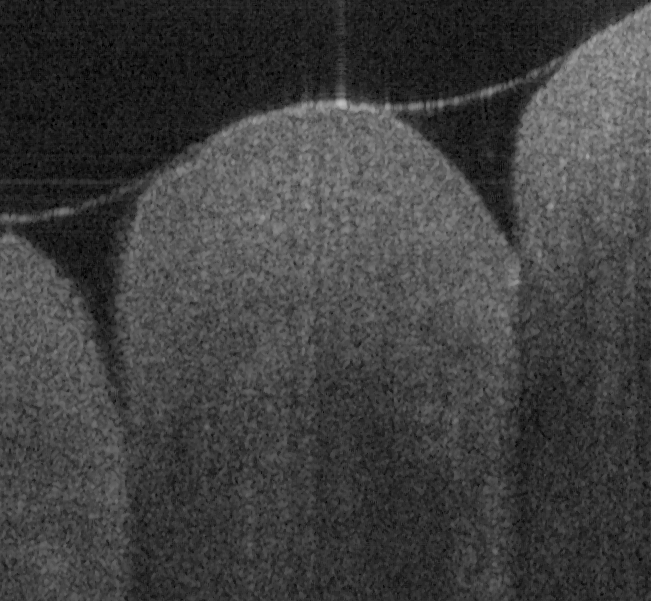

Fig. 16 (a) and (d) show SS-OCT images of human finger in vivo taken using fiber probes #

14 (working distance, depth of field and spot diameter of 1.2 mm 1.1 mm, and 27 m) and #

16 (working distance, depth of field and spot diameter of 0.9 mm 0.33 mm, and 16 m)

acquired by our catheter-based complex SS-OCT using our 3x3 Mach-Zehnder

interferometer with unbalanced differential detection technique with image size of 5x2mm.

The image depth shown in Fig. 16 (a) is slightly larger than that in Fig. 16 (b), but the image

is blurrier in Fig. 16 (a) than that in Fig. 16 (b), which taken by the probe with larger depth of

field and spot size. The image shown in Fig. 16 (b) has higher resolution than that in Fig. 16

(a), which can be seen clearly with finer structures in layer of epidermis (grey arrow), sweat

gland (white arrow), and blood vessel in subcutis layer (black arrow).